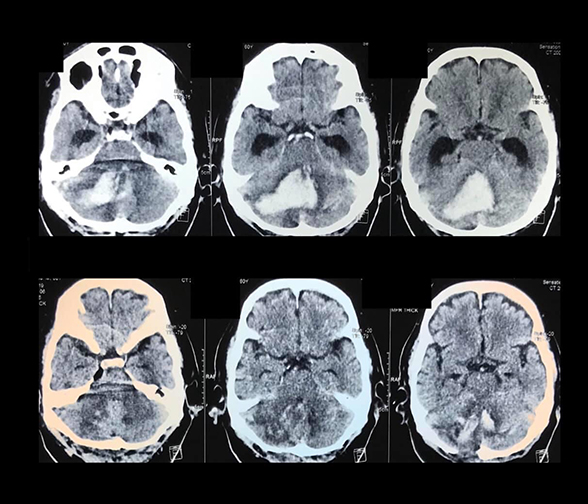

- Clip ligation of brain aneurysms (open microsurgery)

CT scan and/or MRI films or CDs must be brought including pertinent laboratory results/ medical records in order for us to provide you with a sound neurosurgical assessment.